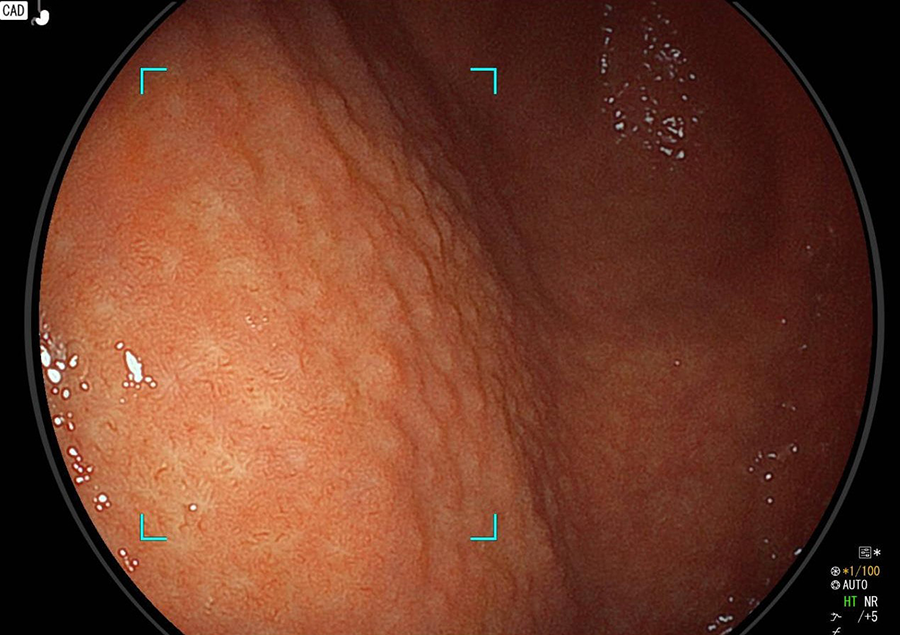

正常の胃

正常の胃粘膜は光沢がありすべすべです。